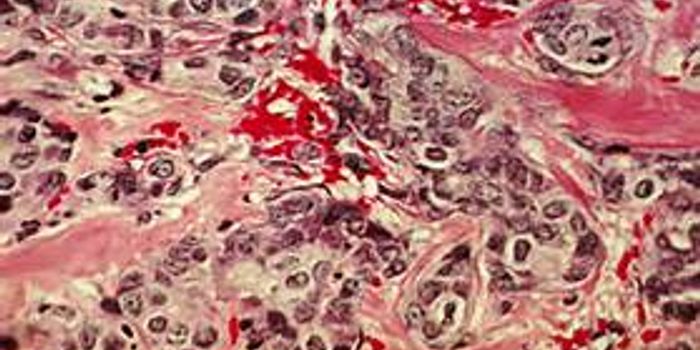

SEP 05, 2014CancerMany adults may find popping a baby aspirin a day lessens the chance of a heart attack.

Researchers have now ... -